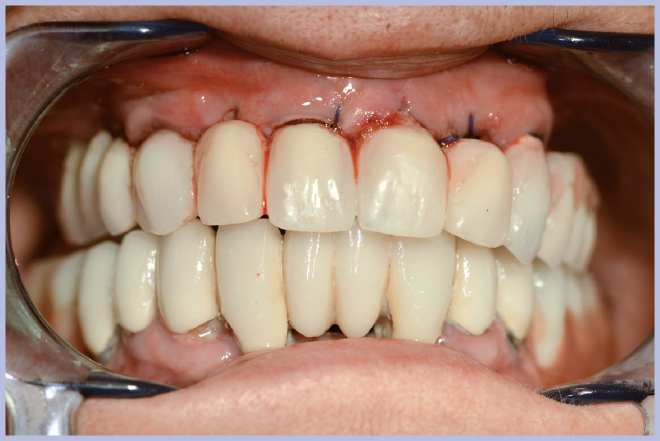

La semplicità della componentistica Leone ha permesso di completare l’intero trattamento in circa 6 ore e mezzo, consegnando alla paziente la protesi ultimata nella stessa giornata della chirurgia (Figg. 11-13).

- Fig. 11 – Consegna della protesi rifinita